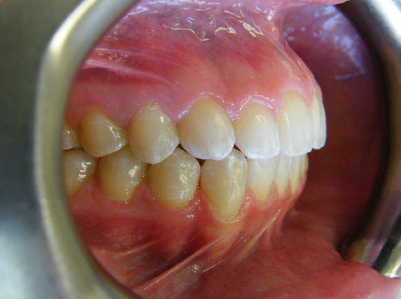

Patient 2: Significant increased overjet and upper and lower crowding.